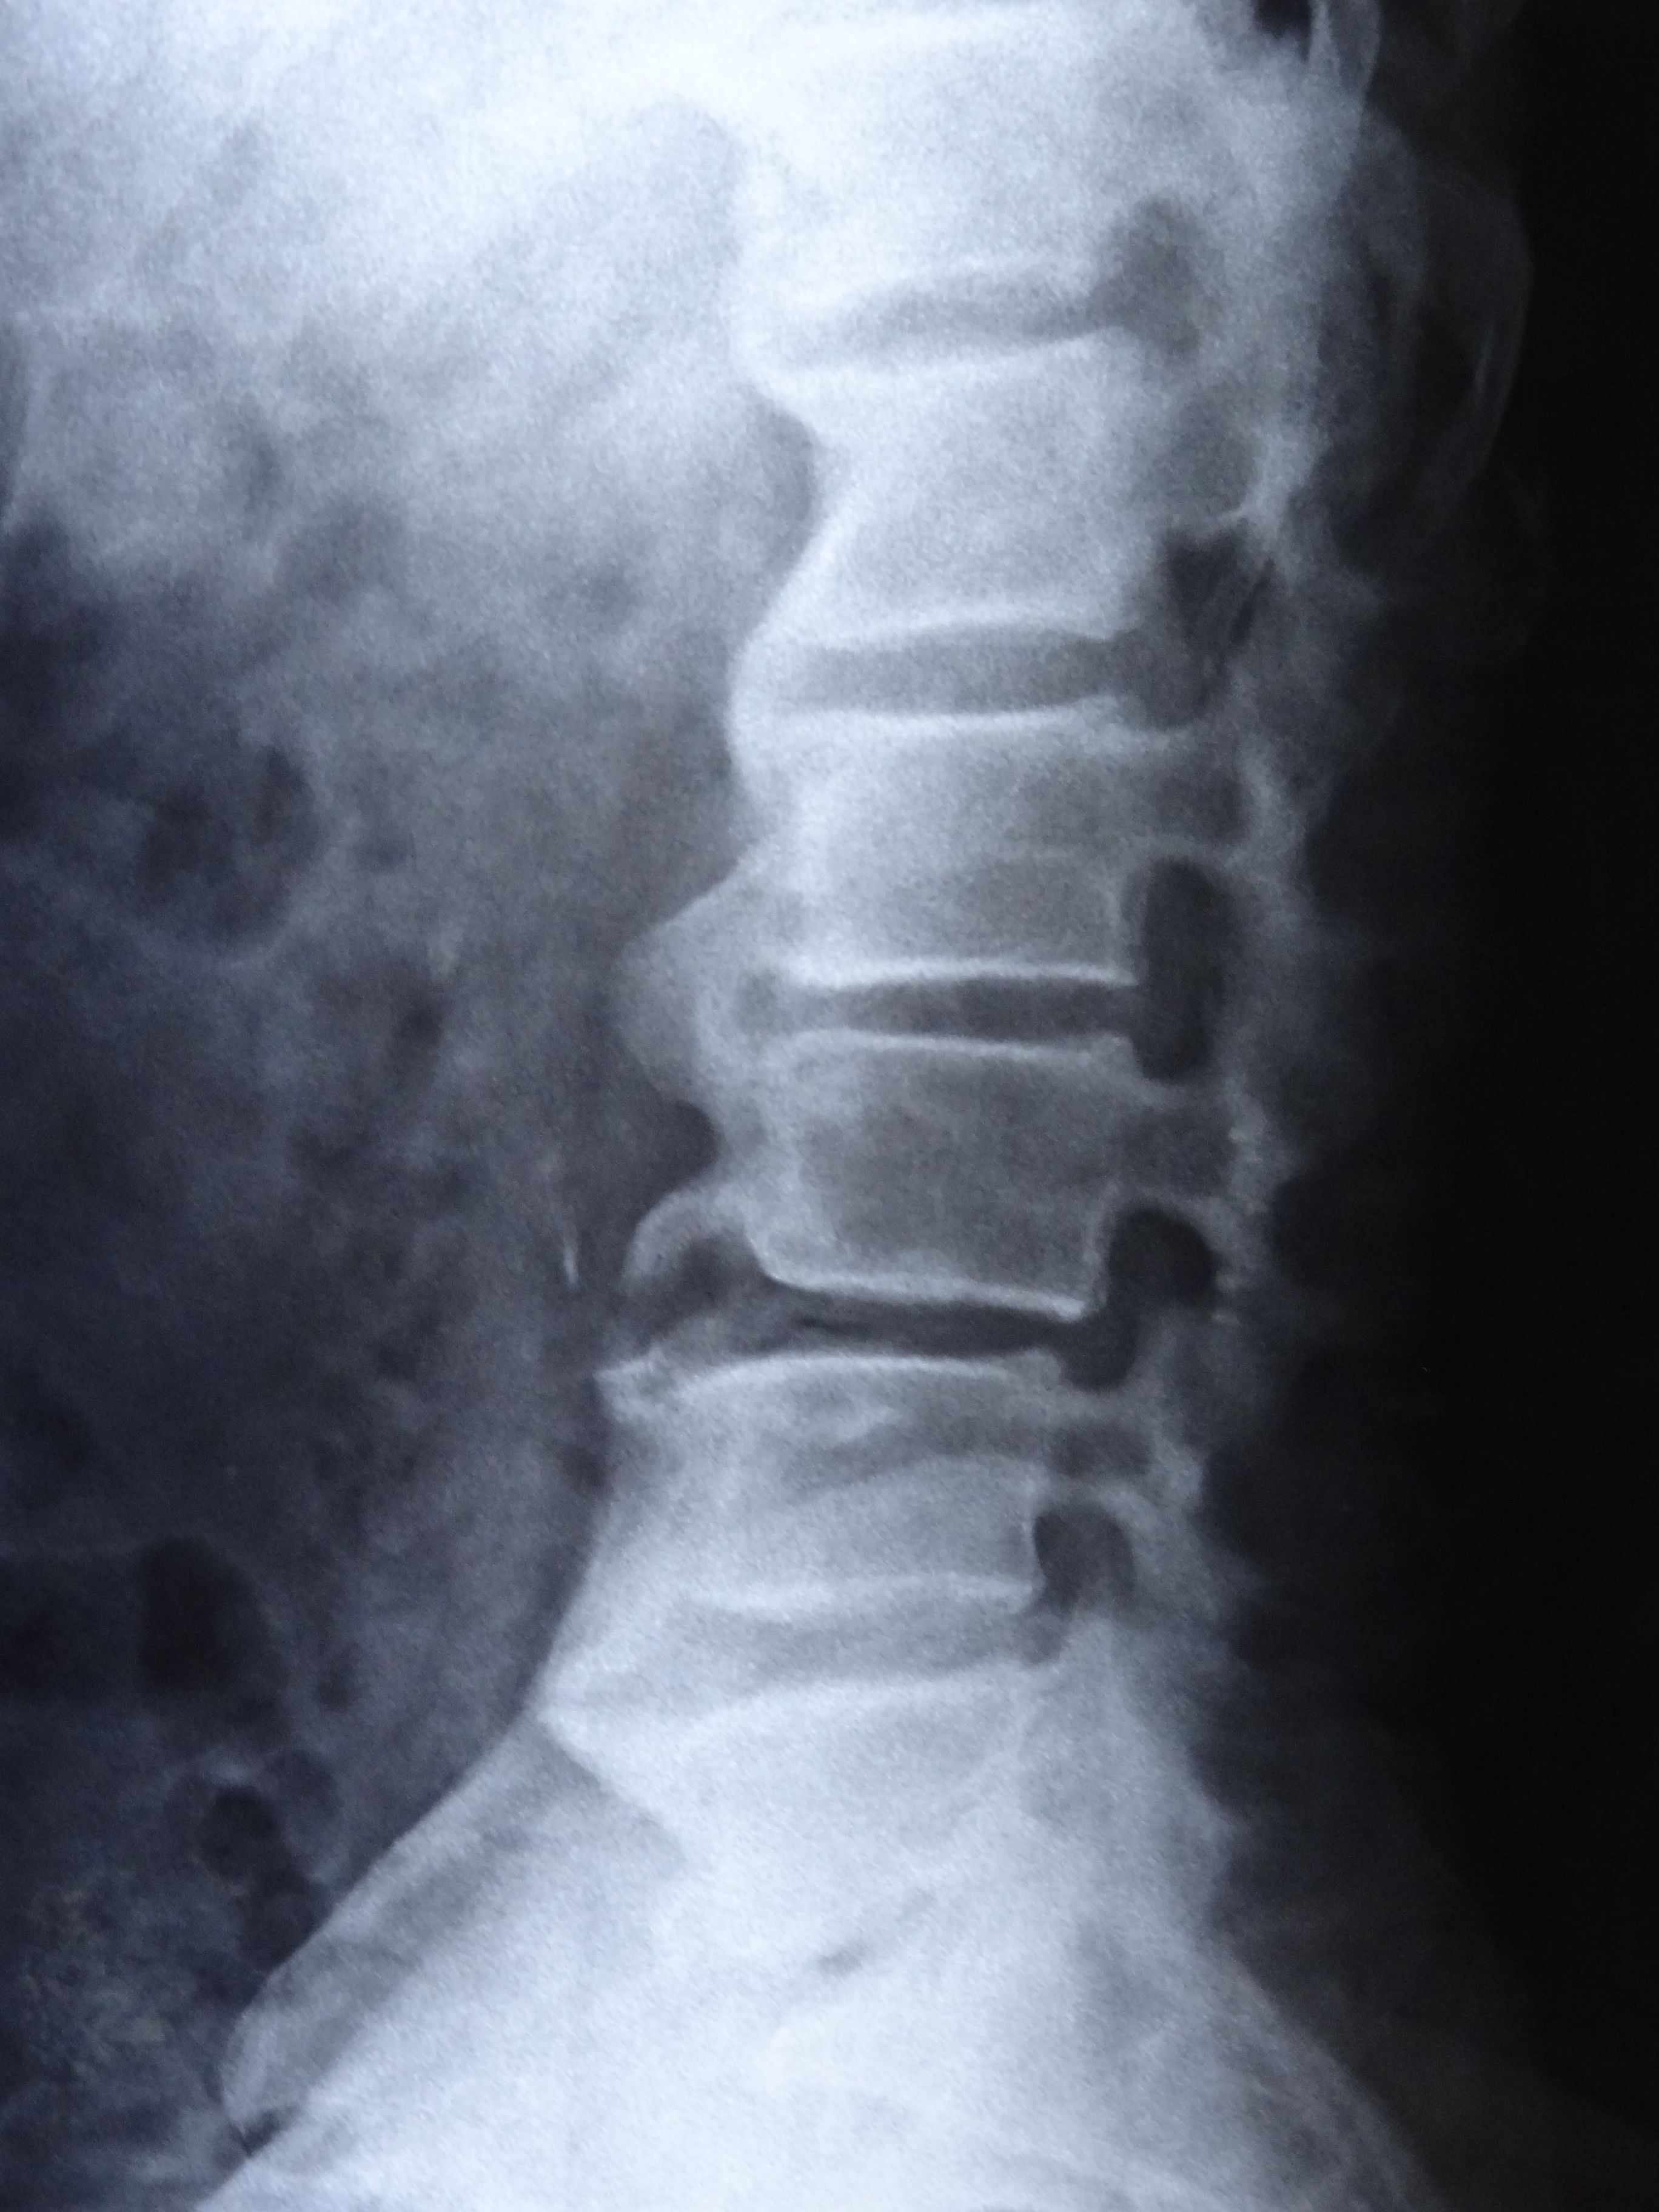

A 70-year-old diabetic and hypertensive male patient visited our clinic with complaints of non-inflammatory back pain since two years. He was heavy built with a BMI of 29 kg/m2. Physical examination revealed limitation of flexion, extension, and lateral flexion of lumbar spine. X-ray of spine revealed flowing calcification of anterior longitudinal ligaments from cervical to lumbar spine with claw osteophytes giving rise to characteristic ‘Melting Wax’ appearance (Panel A: fig A- cervical anteroposterior (AP), fig B- cervical lateral , fig C- lumbar AP , fig D- lumbar lateral) (Panel B: fig E- thoracolumbar AP, fig F- thoracolumbar lateral). Sacroiliac joints were normal (Panel A: fig C- white arrow). The diagnosis was diffuse idiopathic skeletal hyperostosis (DISH or Forestier’s disease) and symptomatic treatment was initiated.